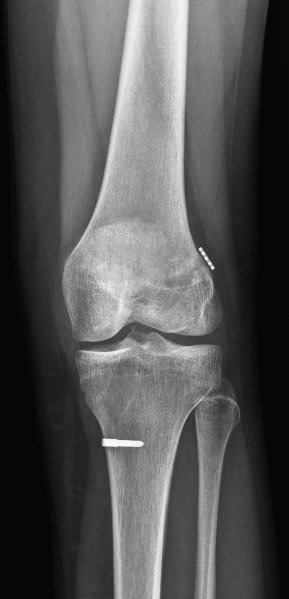

حول كاريا جراحة العظام وإعادة التأهيل عيادة كاريا جراحة العظام وإعادة التأهيل في موغلا ، تركيا تقدم رعاية العظام عالية الجودة ، بما في ذلك العلاجات الجراحية وغير الجراحية من قبل Assoc. البروفيسور الدكتور جيم يالين KILIN وفريقه. وهم متخصصون في الصدمات والإصابات الرياضية وجراحات تقويم المفاصل ، ولديهم خبرة في العلاج الطبيعي لإعادة التأهيل.